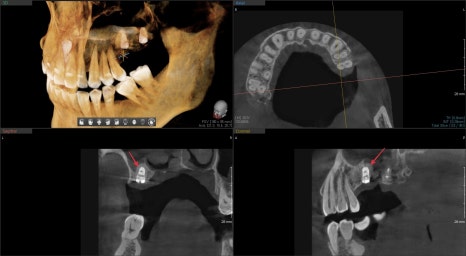

수술 전후 3D CT를 통해 잘 되었는지 평가를 했습니다.

수술 전 비어있던 상악동 공간이

수술 후 흰색으로 표현된 임플란트 주변이 뼈이식재가 주변을 잘 감싸고 있는 것을 볼 수 있습니다.